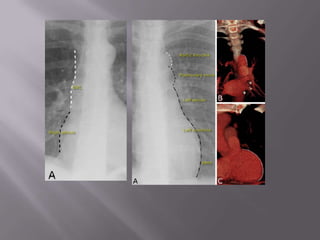

Bit-by-bit checklistTracheaMediastinumHeartCardio-phrenic anglesDiaphragmCosto-phrenic anglesLungsBony cageLateral film, if presentOther findings

TracheaCentral at its upper partDeviates slightly to the right at its lower partIts lucency decreases caudallyComment on:Displacement

CarinaMediastinumCentral with aortic knuckle to the left and SVC to the right

Smooth with no irregularities or festooning

SpineThymusMediastinum